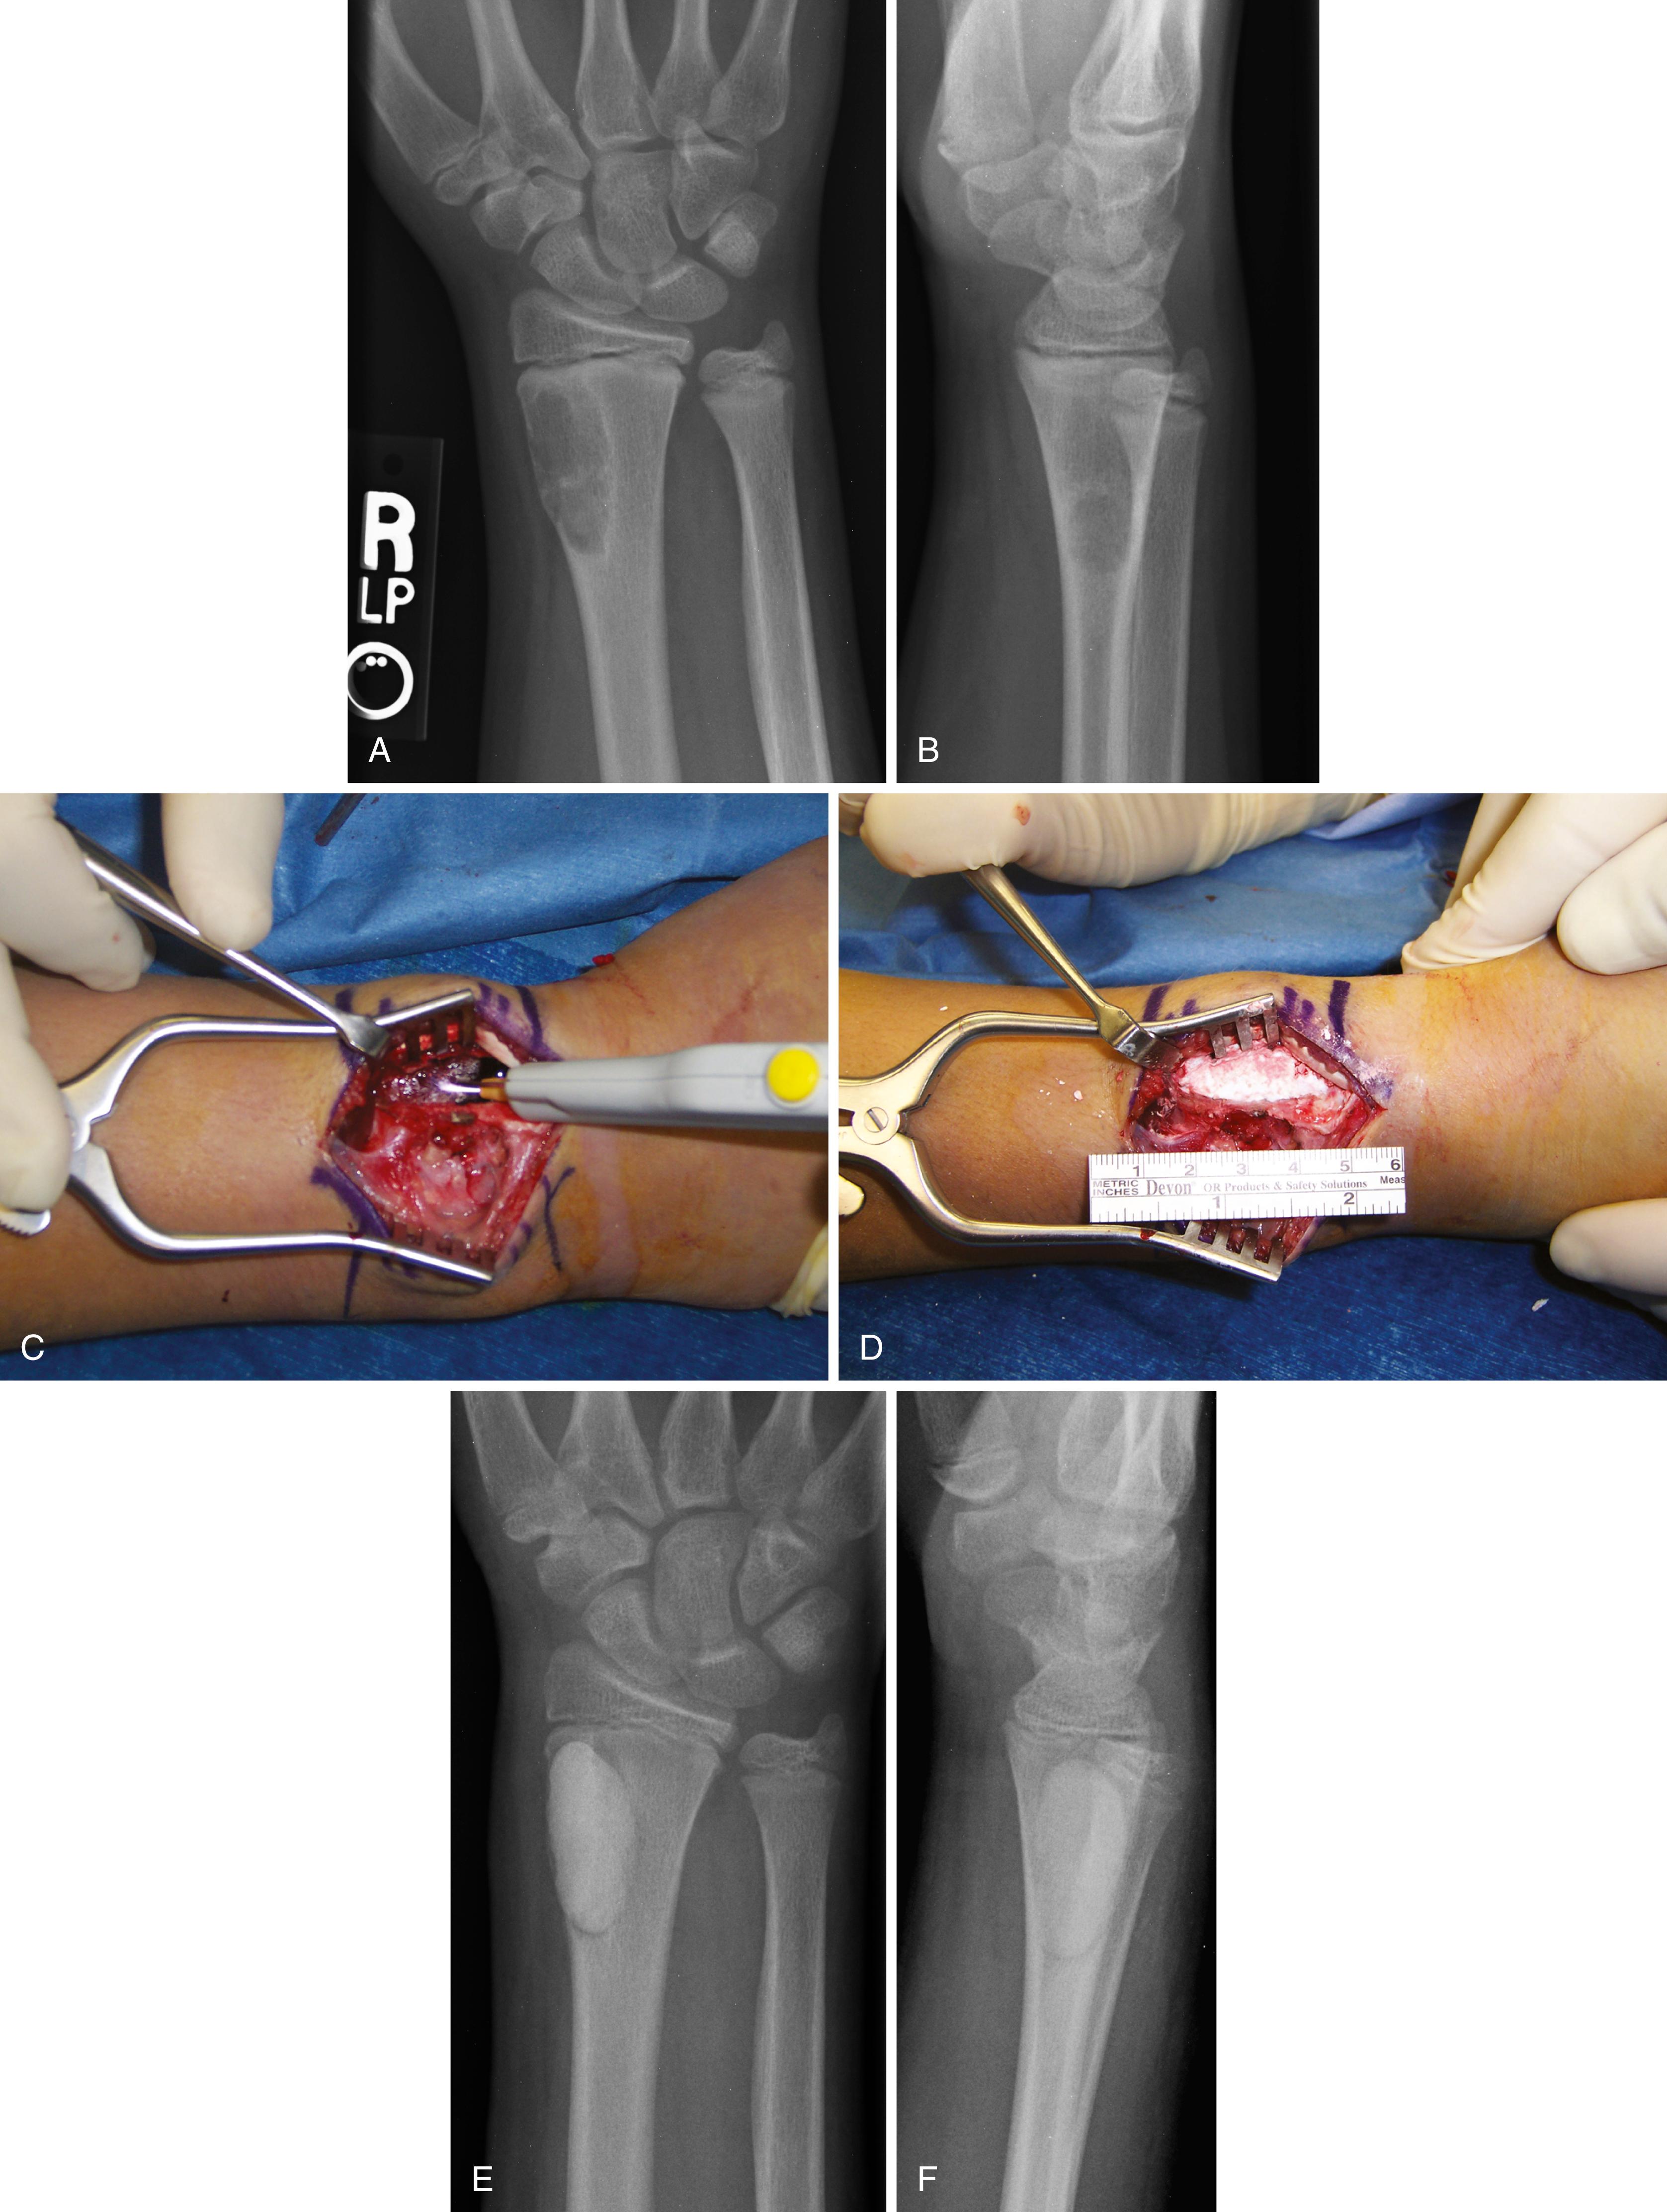

FIGURE 26.4, A and B, Anteroposterior and lateral radiographs of distal radius of 40-year-old woman with pathologic fracture through giant cell tumor. C to E, Axial (C), sagittal (D), and coronal (E) MR images of lesion. F, Intraoperative photograph of tumor in situ. G, Tumor has been resected en bloc.